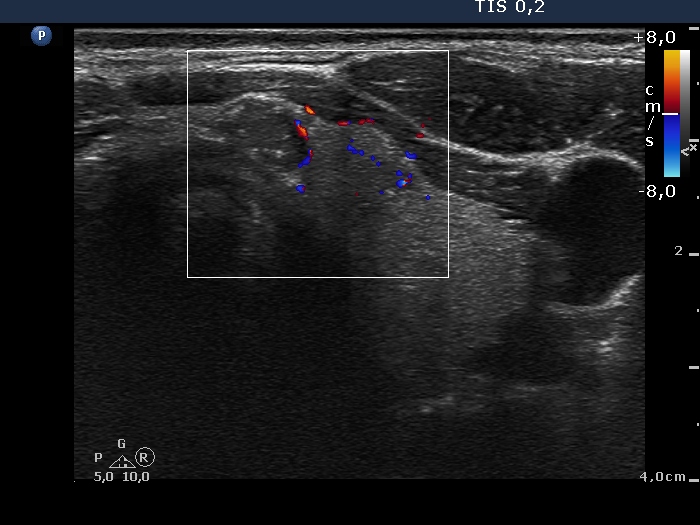

First examination (first to third rows of images):

Ultrasonography: The thyroid was echonormal. There were several hypoechogenic nodules presenting microcalcifications in both lobes and in the isthmus. There was a similar lesion under the lower pole of the left lobe. The vascularization of the lesions was variable.